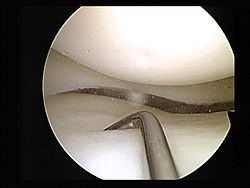

Resultados adversos después de la meniscectomía artroscópica parcial: estudio de 700 000 procedimientos en la base de datos nacional de Inglaterra

Lancet. 24 de septiembre de 2018InterpretaciónEn general, el riesgo asociado con someterse a una meniscectomía parcial artroscópica fue bajo. Sin embargo, algunas complicaciones poco frecuentes pero graves (que incluyen embolia pulmonar e infección) están asociadas con el procedimiento y los riesgos no han disminuido con el tiempo. En vista de la incertidumbre sobre la efectividad de la meniscectomía parcial artroscópica, una apreciación de los riesgos relativos es crucial para los pacientes y los médicos. Nuestros datos proporcionan una base para la toma de decisiones y el consentimiento.